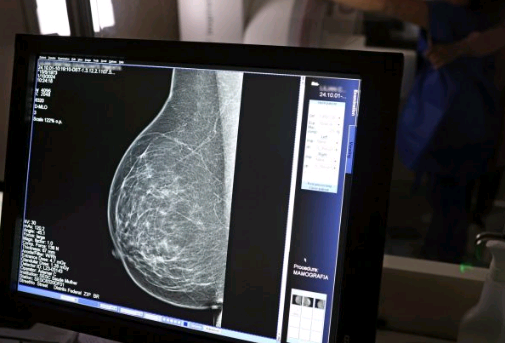

Baixa adesão à mamografia dificulta diagnóstico de câncer de mama

Cerca de 30% a 40% dos casos no Brasil ainda são identificados em fases avançadas

Baixa adesão reduz significativamente as possibilidades de tratamento eficaz. Foto: José Cruz/Agência Brasil

Dados do Panorama do Câncer de Mama revelam que o Brasil possui menos de 24% de cobertura mamográfica, bem abaixo dos 70% recomendados pela Organização Mundial da Saúde (OMS). O estudo também aponta disparidades raciais significativas: 44% das mulheres pretas e pardas recebem diagnóstico tardio, contra 36% das brancas. Especialistas alertam para a necessidade de melhorar o acesso e a conscientização sobre a importância do rastreamento.

Segundo estudos, essas mudanças no estilo de vida podem diminuir em até 30% as chances de desenvolver a doença. Já a prevenção secundária, igualmente crucial, envolve o rastreamento sistemático por meio de mamografias anuais a partir dos 40 anos para a população em geral, com início mais precoce para mulheres que apresentem histórico familiar significativo ou mutações genéticas conhecidas que aumentem o risco. Muitas mulheres enfrentam dificuldades logísticas, como a distância dos serviços de saúde e horários incompatíveis com suas rotinas, o que contribui para baixa adesão, além da falta de conscientização sobre a importância da mamografia.

A professora Maria Del Pilar enfatiza que o prognóstico está diretamente ligado ao estágio do diagnóstico. Enquanto tumores detectados precocemente têm alta chance de cura, cerca de 30% a 40% dos casos no Brasil ainda são identificados em fases avançadas, o que reduz significativamente as possibilidades de tratamento eficaz.